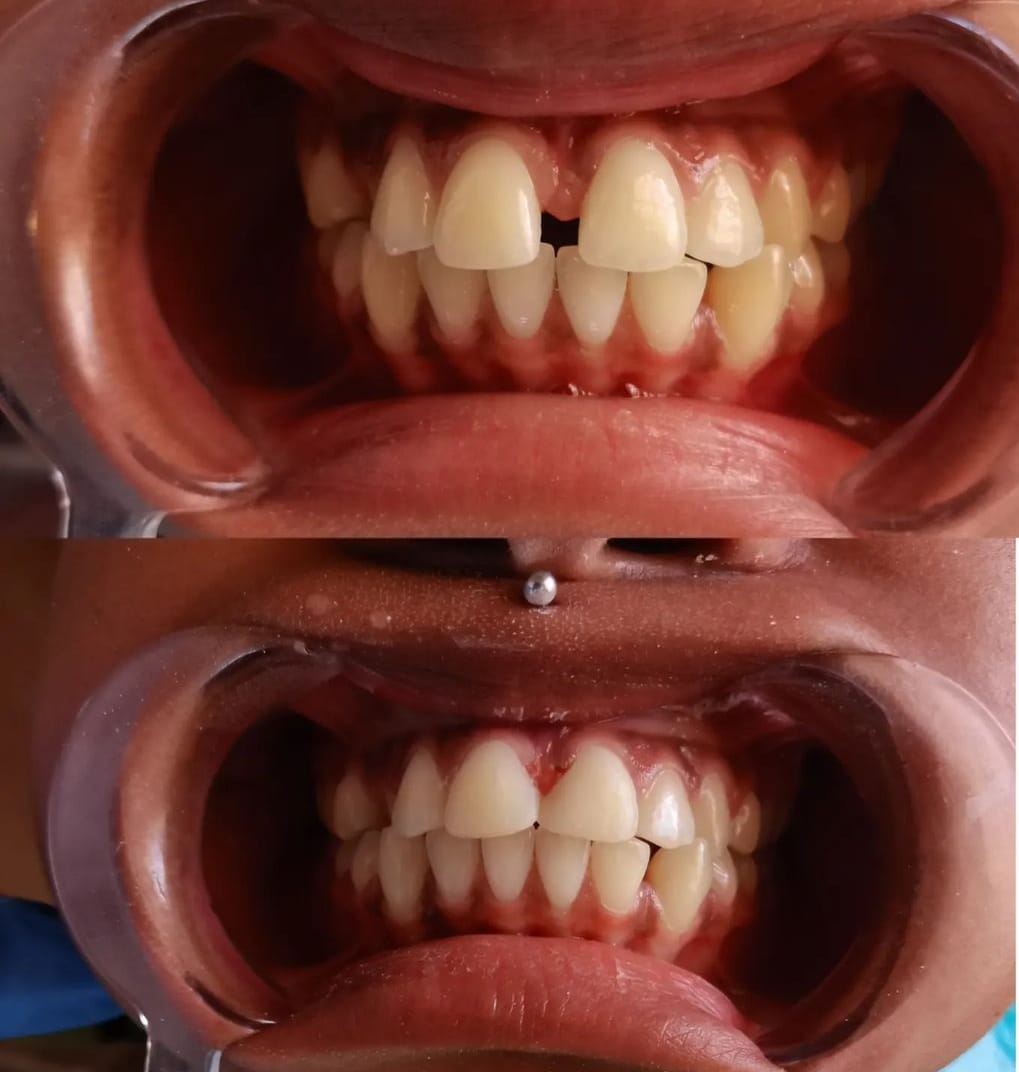

Our Latest Work